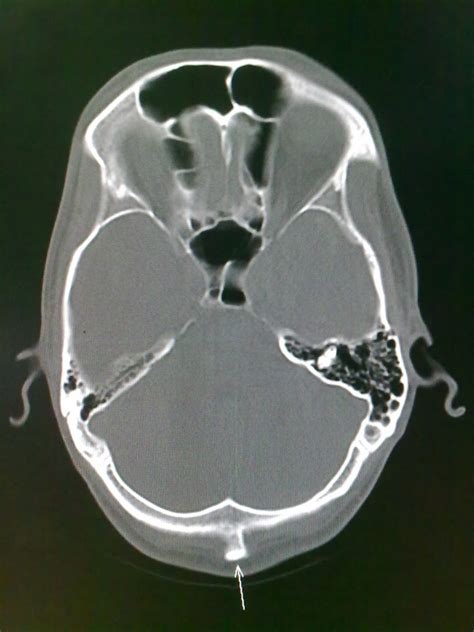

- Imaging Studies: CT and MRI scans often reference the EOP as a landmark for orienting cross-sectional views of the posterior cranial fossa and occipital region.

Situated at the midline of the occipital bone—the largest flat bone of the skull—the EOP lies just below the foramen magnum and near the posterior border of the lambdoid suture. Its exact prominence varies across individuals due to differences in skull shape, bone density, and genetic factors. The EOP is easily palpable in most people and is commonly referenced in medical imaging, chiropractic assessments, and forensic anatomy.